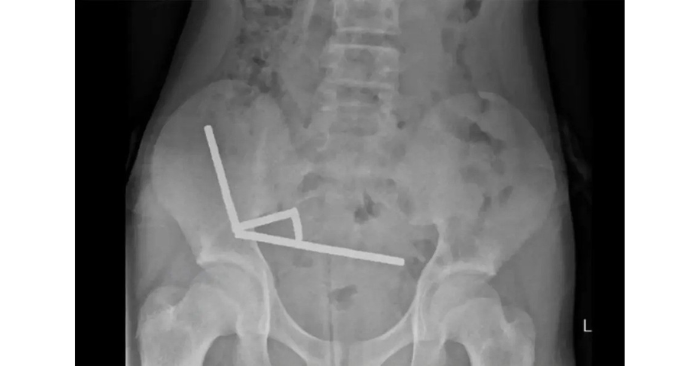

Tuy nhiên, khi phẫu thuật, các bác sĩ lấy ra gần 200 viên nam châm từ ruột bệnh nhi. Phim X-quang cho thấy bốn chuỗi nam châm mắc kẹt ở các đoạn khác nhau trong đường tiêu hóa, hút chặt vào nhau và cản trở lưu thông máu đến các mô lân cận.